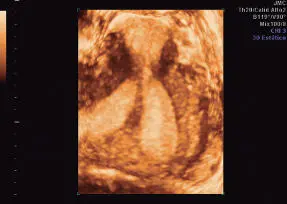

Adenomiosis

Es la presencia de tejido endometrial (estromas y glándulas) en el espesor del miometrio. En la ultrasonografía, es característico observar el cuerpo uterino globuloso, heterogenicidad miometrial, con pérdida de unión entre el miometrio y endometrio. Puede existir asimetría en relación al grosor entre la pared miometrial anterior y posterior, y la heterogenicidad puede presentarse en un área focal nodular poco definida (adenomioma), semejando la imagen ecográfica de un mioma. Pueden observarse áreas econegativas en su espesor. Su diagnóstico por ultrasonografía es difícil. Con frecuencia se observa en conjunto con la presencia de miomas. Debe recordarse que el diagnóstico de adenomiosis se plantea en términos clínicos y el diagnóstico definitivo es a través del estudio histológico del útero ( Figuras 16-49y 16-50).

Figura 16-50.Adenomiosis. Corte transverso